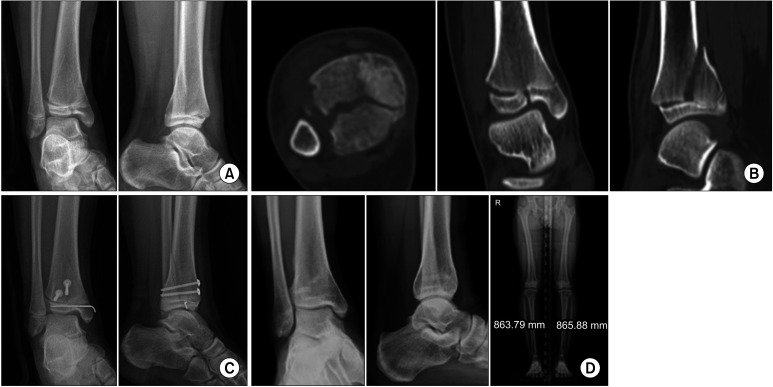

背景:本研究旨在比较关节镜下复位经皮内固定与切开复位内固定治疗踝关节内骺骨折的临床效果。方法:我们对2016年至2021年间连续接受关节内骨骺踝关节手术的患者进行了回顾性研究。共纳入88例患者,分为2组:关节镜复位组(AS组)和常规切开复位组(OR组)。15名患者被分配到AS组,30名患者从OR组中选择,考虑到人口统计学、骨折形态和随访时间,采用2:1的倾向评分匹配。临床结果采用足踝预后评分(FAOS)进行评估,而影像学评估用于评估骨愈合和关节面一致性。我们还分析了并发症,如感染、骨不连、成角、腿长差异和创伤后骨关节炎。结果:组间随访时间统计学差异有统计学意义(p = 0.04);然而,成功的倾向评分匹配消除了组间人口统计学和骨折配置变量的差异(均p < 0.05)。创伤的病因在其他变量上相似(p < 0.05)。两组术后FAOS均为良至优,两组间差异无统计学意义(p < 0.05)。两组均实现骨愈合,无骨不连,骨愈合时间和关节一致性无显著差异(p < 0.05)。虽然OR组并发症发生率高于AS组(3例vs. 0例),但差异无统计学意义(p = 0.083)。结论:关节镜复位和经皮内固定似乎是治疗关节内骨骺骨折的有效、微创选择,其结果与切开复位相当,并发症发生率低。

Methods: We conducted a retrospective review of consecutive patients who underwent intra-articular epiphyseal ankle surgery between 2016 and 2021. A total of 88 patients were included and divided into 2 groups: the arthroscopic reduction group (AS group) and the conventional open reduction group (OR group). Fifteen patients were allocated to the AS group, and 30 were selected from the OR group using propensity score matching in a 1 : 2 ratio, considering demographics, fracture configuration, and follow-up period. The clinical outcomes were assessed using the Foot and Ankle Outcome Score (FAOS), while radiological evaluations were used to assess bone union and the congruence of the articular surface. We also analyzed complications such as infection, nonunion, angulation, leg length discrepancy, and posttraumatic osteoarthritis.

Results: There was a significant difference in follow-up periods between the groups in terms of demographics (p = 0.04); however, successful propensity score matching eliminated any differences in demographic and fracture configuration variables between the groups (all p > 0.05). The etiology of trauma was similar across other variables (p > 0.05). Postoperative FAOS ranged from good to excellent in both groups, with no significant differences between them (all p > 0.05). Both groups achieved bone union without nonunion, with no significant differences in bone union time or joint congruency (all p > 0.05). Although there were more complications in the OR group than in the AS group (3 vs. 0 cases), this difference was not statistically significant (p = 0.083).

Conclusions: Arthroscopic reduction and percutaneous fixation appear to be effective, minimally invasive options for the treatment of intra-articular epiphyseal ankle fractures, offering outcomes comparable to open reduction with a low rate of complications.